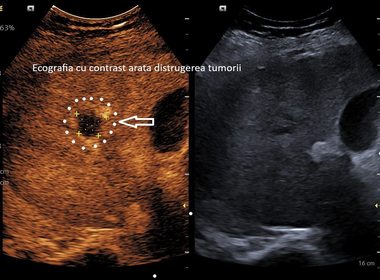

Spitalul Clinic Judeţean de Urgenţă Craiova anunţă, luni seară, o premieră în unitatea medicală, respectiv prima ablaţie cu microunde a unei tumori hepatice. La doar o lună după intervenţie, investigaţiile imagistice au confirmat distrugerea completă a tumorii.

Potrivit datelor transmise de reprezentanţii spitalului, la doar o lună după intervenţie, investigaţiile imagistice au confirmat distrugerea completă a tumorii.